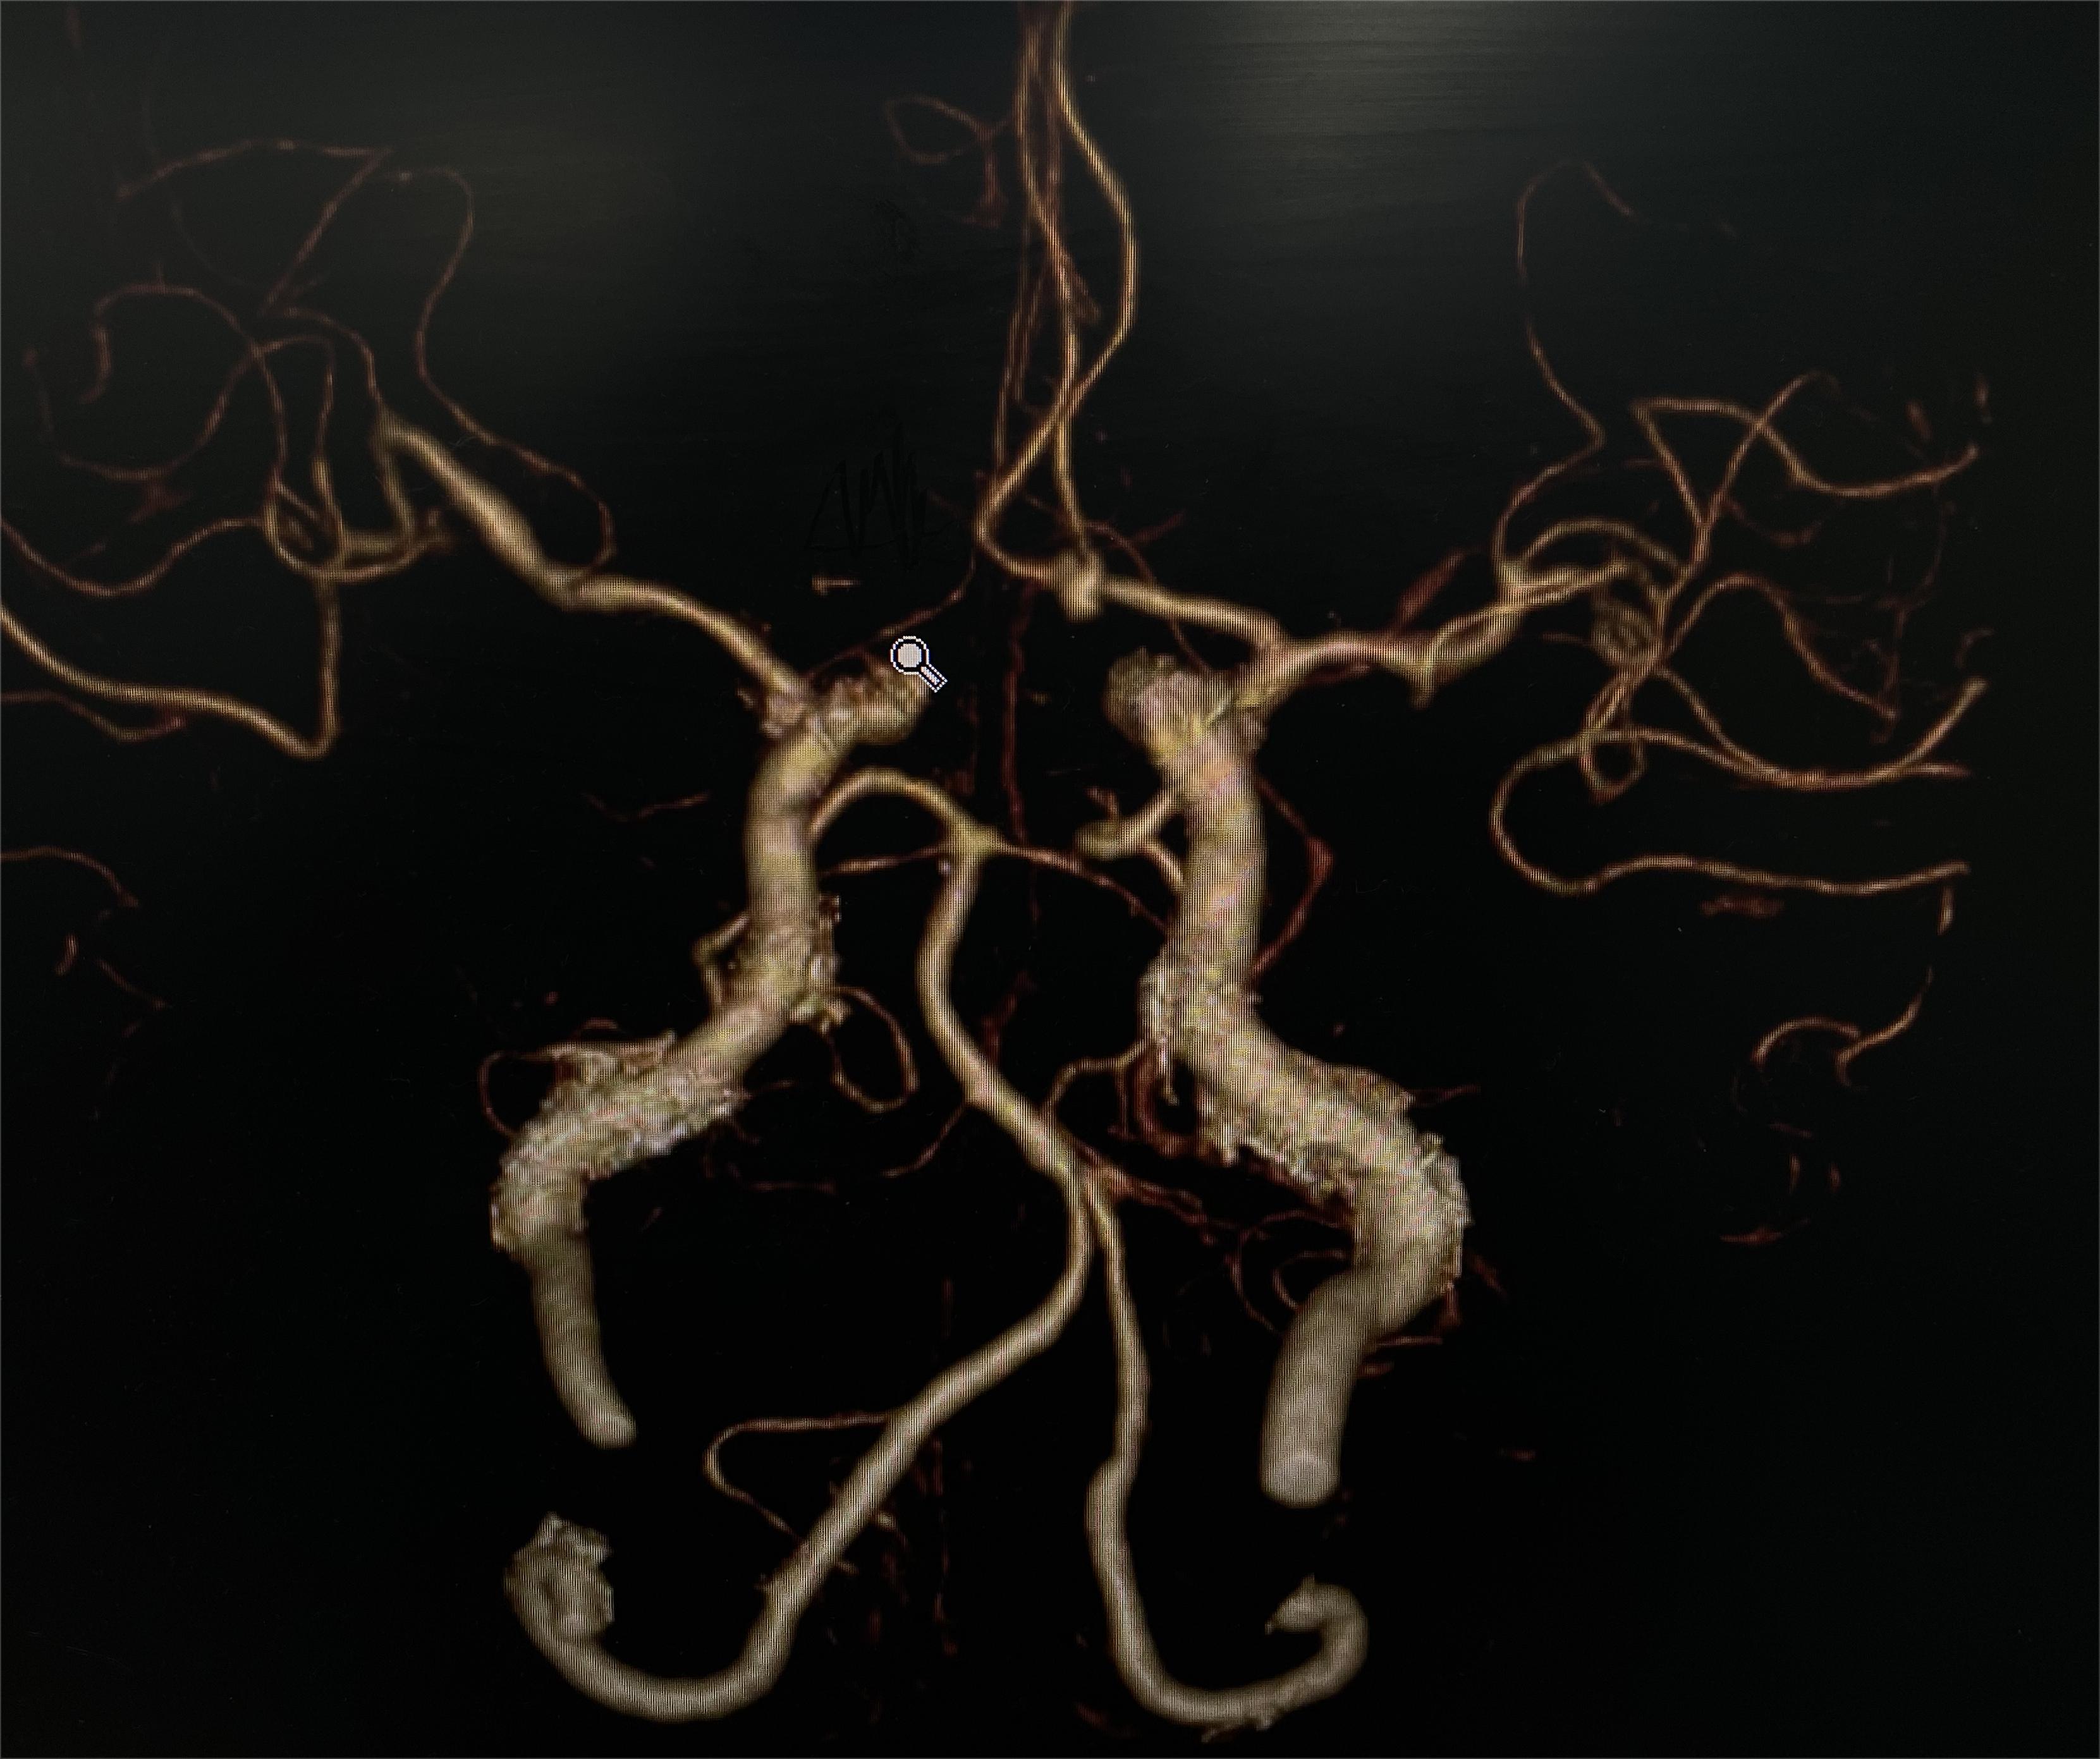

术前CTA

术前CTA